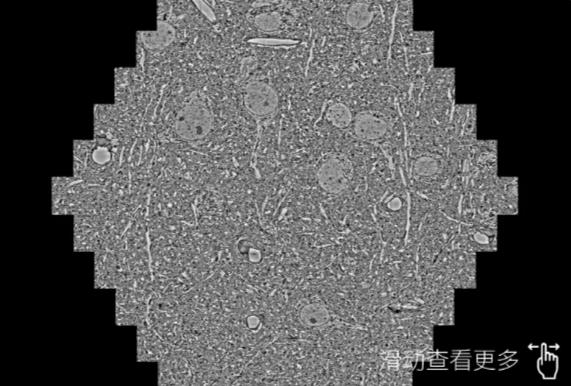

鼠脑切片。左图使用嘉峪关蔡司嘉峪关扫描电镜MultiSEM706对165μmx143pm面积区域成像,耗时仅需1.5秒。右图为鼠脑切片中30μm区域放大效果。样品由芝加哥大学B.Kasthuri提供。

使用蔡司高速嘉峪关扫描电镜MultiSEM对1mm²人脑皮层组织进行高分辨成像,并对其中的各种细胞结构进行三维重构分析。左图展示了2x3mm²组织平面中锥体神经元的三维重构效果。右图显示了局部体积神经元三维重构。图像由哈佛大学chtman实验室提供,渲染图由D. Berger 制作。